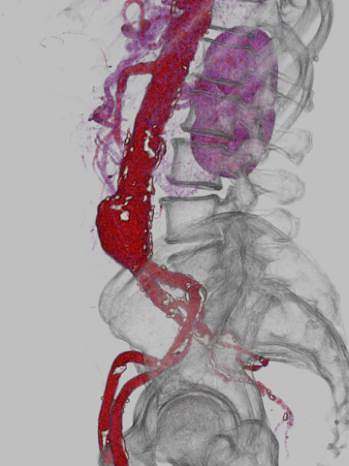

Angioscanner : anévrysme de l’aorte abdominale

Angioscanner avec reconstruction 3D d’un anévrysme de l’aorte

Angioscanner avec reconstruction 3D d’un anévrysme de l’aorte abdominale